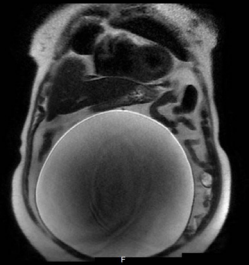

A 90-year-old, woman presented with a 2-year history of diffuse abdominal pain, discomfort and nonspecific symptoms such as anorexia, nausea, vomiting. The patient lives in the village. Have not applied to a doctor before. Pre-Surgery Patient has not received any treatment. On physical examination, a huge (nontender) abdominal mass was palpated at the central abdomen. MRI of the whole abdomen demonstrated a huge cyst in the abdomenmeasuring 40x35cm (Figure 1).

Figure 1 Giant cyst in the MRI image.